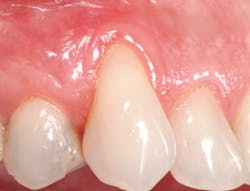

In our ongoing efforts to provide patients with the best standard of care, there are many products that are used to help the clinician, hygienist, and patient obtain optimal results. Straumann Emdogain when combined with a coronally advanced flap (CAF) is one such product. This product is a biology-based and scientifically proven solution designed to promote predictable regeneration of hard and soft tissues lost to periodontal disease for a natural-looking result.

Without the use of Emdogain, the periodontist performs a "periodontal plastic surgery" procedure in which connective tissue taken from the patient's palate is used to cover the exposed root. With the use of Emdogain, patients tend to have less pain and discomfort because there is no need for a second surgical site.5 Straumann Emdogain is designed to promote the regeneration of hard and soft tissues that anchor your teeth. When patients learn this, treatment compliance increases.

Emdogain is designed to reverse recession naturally. How? In much the same way stem cells work to generate new cell growth, Emdogain uses proteins - which the body produces naturally - to regenerate lost gum tissue, bone, and the structures that anchor teeth to bone.6

Creating a successful dental hygiene department does not happen by chance. What is needed is a commitment to new philosophies and a continual effort to implement new skills, materials, and treatment protocols. Treatment of gingival recession is just one way to do this. Don't let the next patient with gingival recession walk out of your operatory without options. With more than 400 clinical studies demonstrating its effectiveness and proven, long-term results,7 Emdogain is designed to give your patients the chance to reverse their recession before the esthetics of their smile could become compromised.